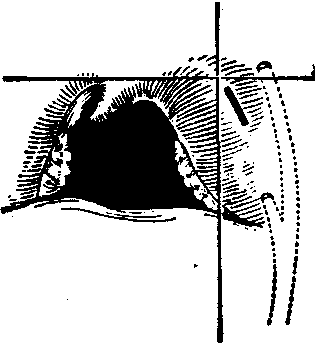

扁桃体周围脓肿切开引流部位

脓肿位于前上方者,如不易确定切口部位可沿悬雍垂根部作一假想水平线,再于舌腭弓游离缘的下端作一假想垂直线,于此两线交点处或稍外侧切开。脓肿位于后上方者,可不作切口,直接用止血钳自咽腭弓上端插入扩张引流。

本病初期,脓肿尚未形成时,其治疗与急性扁桃体炎基本相同。除全身应用抗生素或清热解毒之中草药外,可行颈部热敷、理疗或下颌角封闭疗法等。脓肿如已形成则应行切开引流术。切开引流术常于粘膜表面麻醉下进行。也有人主张采用迷走-交感神经阻滞麻醉。在最隆起处或穿刺有脓处切开粘膜及粘膜下组织,长约1cm,再插入止血钳,进入脓腔,扩张切口,排出脓液,不放置引流物。以后每日可再行扩张一次,直至脓液排尽。